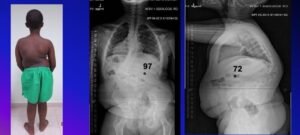

Most common type of congenital deformities which result from vertebral malformation during the gestational period. Family history is rare: 13/1,250 Patients positive F-Hx (Winter, 1983). They are grouped as:

Two main types of malformation are described and include formation and segmentation defects.

- Formation defects: Missing parts of vertebral (Hemivertebra most common)

- Segmentation defects: Failure of part if the vertebral to separate Unsegmented bars).

True incidence unknown but in general 25% of curves do not progress, 25% of curves slowly progress and 50% are very progressive.